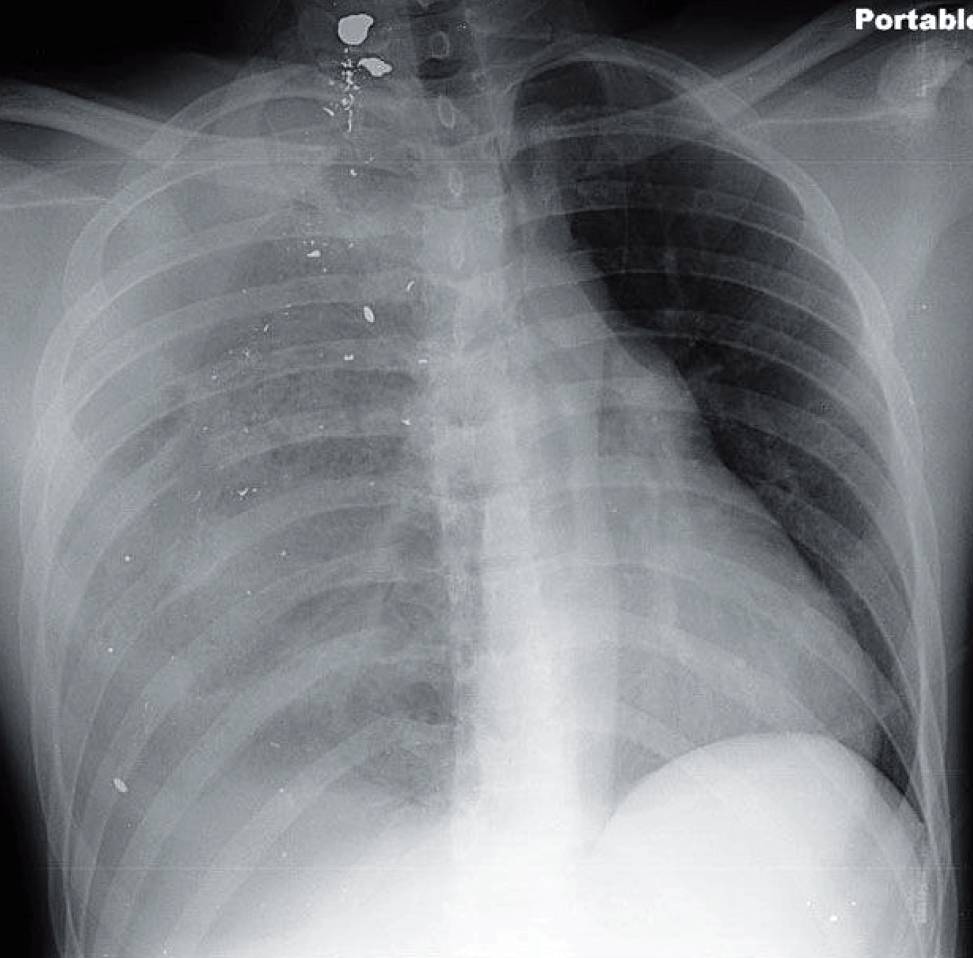

- Single-view portable radiograph shows multiple bullet fragments on the right with shift of the heart and mediastinum leftward. Pulmonary contusions and lacerations are seen near the bullet fragments.

- Increased opacification is seen in the right apex and increased lucency in the right base.

Although the tension component may prompt one to consider pneumothorax, the density of the pleura is somewhat mixed. The combination of pleural densities is indicative of either a tension hydropneumothorax or a tension hemopneumothorax.